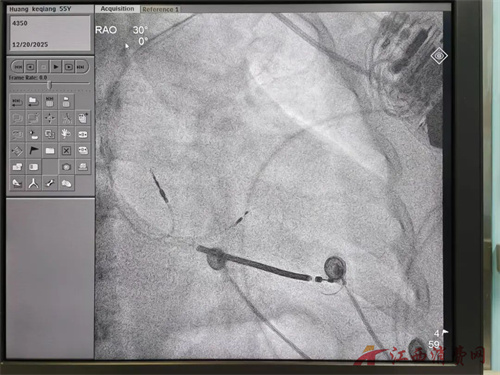

在黄瑛主任医师的指导下,由王媛媛医生等骨干成员组成的手术团队,凭借丰富的介入经验与默契配合,成功完成了这例高难度手术。手术采用微创方式,患者在局部麻醉下完成,术后恢复迅速,次日即可下床活动。

一个月后复查的结果令人欣喜,心脏超声:射血分数从37%提升至46%,左心室大小从51毫米回缩至48毫米。这意味着心脏泵血力量显著增强,扩大的心脏开始“缩小”。心电图:原有的左束支传导阻滞图形明显改善,QRS波宽度从大于187毫秒显著缩短至120毫秒,阻滞的左室开始同步收缩,心室的收缩活动基本恢复了协调同步。

这些客观数据清晰地证实了Lot-CRTD治疗的有效性,同时朱先生自觉胸闷、气短水肿的症状得到了完全缓解,已经开始进行运动康复了。